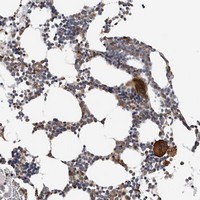

- Immunohistochemical staining of human bone marrow with C7orf62 polyclonal antibody (Cat # PAB21609) shows strong cytoplasmic positivity in megakaryocytes at 1:10-1:20 dilution.

- Immunohistochemistry (Formalin/PFA-fixed paraffin-embedded sections)